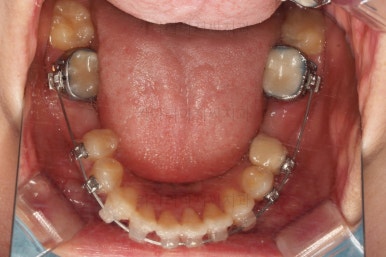

어느새 틈도 다 닫히고요.

마무리 과정만 남았습니다.

틈이 다 없어졌고, 교합도 양호합니다.

무엇보다 임플란트 없이 결손부위가 깔끔하게 채워졌고요.

매우 다행으로 사랑니도 다 있었기 때문에 마치 큰 어금니가 다 있는 것과 같은 상황이 되었습니다.

역설적이게도 손상된 큰 어금니가 없었던 부위는 작은 어금니를 발치함으로 인해 오히려 치아 갯수가 모자라 보이는 상황까지 왔네요.(어금니가 결손된 부분이 더 자연스럽게 보이는 상황)